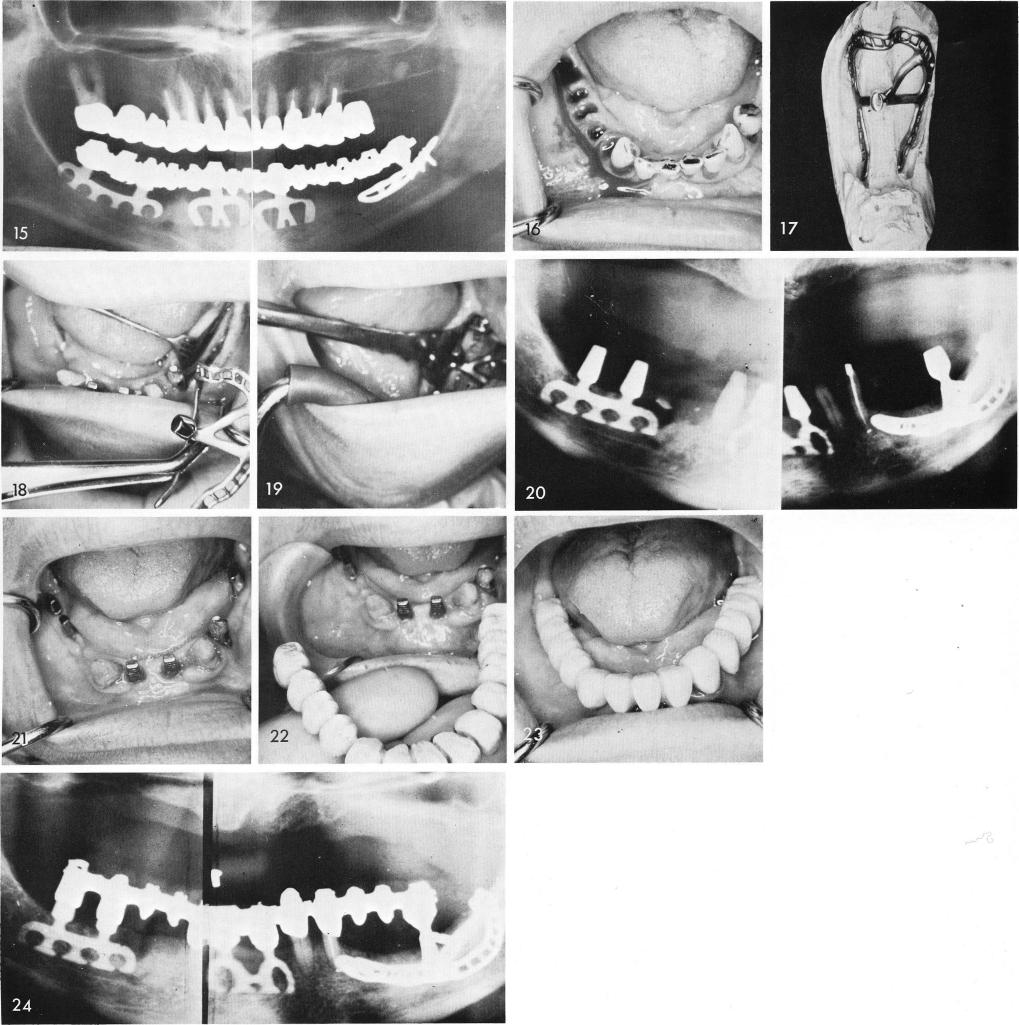

When some teeth are present it is not that imperative to first be certain that the subperiosteal implant must fit as some of the remaining teeth can be utilized to help support the bladevents and give the patient a temporary plane of occlusion, fig. 16. The impression for the subperiosteal implant can be taken at the same time the bladevents are inserted, figs. 17, 18, 19, 20. After healing, fig. 21, the acrylic over gold restoration is cemented, figs. 22, 23. A final x-ray, fig. 24.

1 Post operative Xray of Mandibular subperiosteal and bladevent implants